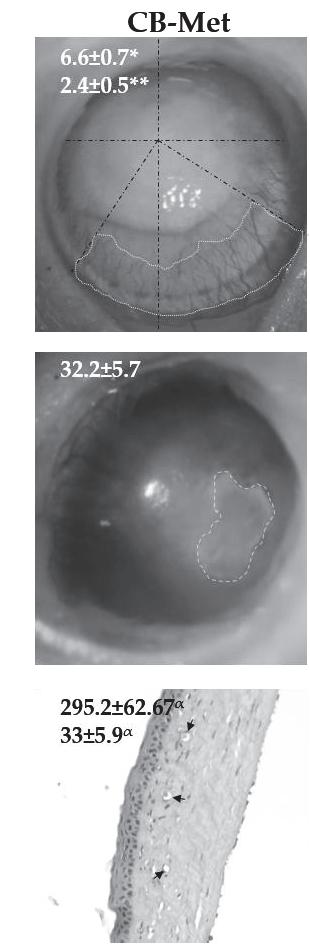

Weevaluatedcornealwoundhealingmediatedbytheextractsinthealkali-burncornealmodel. Figure 1ashowsthatthetreatedgroupshadasignificantreductionincornealopacityscoreandCNV areacomparedtotheCB-Veh(p < 0.05and p < 0.001,respectively).However,CNVintheCB-Met treatedgroupwaslowerthantheCB-Hexgroup(p < 0.05)andfurthermoredidnotshowasignificant increaseinthepercentageofre-epithelialization(Figure 1b).

UsingHE-stainedslides(Figure 1c),thenon-CBgrouphadanaveragecornealthicknessof336.7 ± 39.5 μm,withanintactepithelialandstromallayer.Therewereneitherinflammatorycellsnorblood vessels.Conversely,cornealintegrityintheCB-Vehgroupwasseverelyimpaired,withalossofthe epithelialcelllayersanddisruptionofstromalcollagenfibers.Thecornealthicknessinthisgroupwas 592.3 ± 112.1 μm,withanaveragecellinfiltrationof81 ± 11.9%.CornealthicknessintheCB-Hexgroup was427.2 ± 113.7 μm,whichwassignificantlyreducedcomparedtotheCB-Veh),withareductionin cellinfiltration(40 ± 8.1%).Similarly,theCB-Metgroupshowedadecreaseincellinfiltration(33.2 ±

2019, 11,1184

5.9%)andcornealthickness(295.2 ± 62.67 μm)(p < 0.001)comparedtoCB-Veh.Cornealthicknessin theCB-Metgroupwasnotsignificantlydifferentfromthatofthenon-CBgroup.

Figure1. Methanol(Met)andhexane(Hex)extractsof Cucurbitaargyrosperma seedinchemicallyburned corneas(CB)comparedtotheuntreatedgroup(CBcorneastreatedwiththevehicle,CB-Veh).(a)Average ofopacityscore(OPA)andcornealneovascularizationarea(CNV)inmm2 .(b)Re-epithelialization percentage(RE).(c)Cornealthicknessinmicrons(THK)andinfiltrationcellpercentage(INF).Average value ± SD;* p < 0.05;** p < 0.01,and α p < 0.001comparedtoCB-Veh. @ p < 0.05comparedtoCB-Met. Graydottedlinesshowstudiedarea,andblacklinesarethegeometricalaxis.CB-Hex:CBcorneas treatedwithhexanicextract;CB-Met:CBcorneastreatedwithmethanolicextract.Arrowsindicatethe lumenofstromalbloodvessels.(Scalebar = 100 μm).